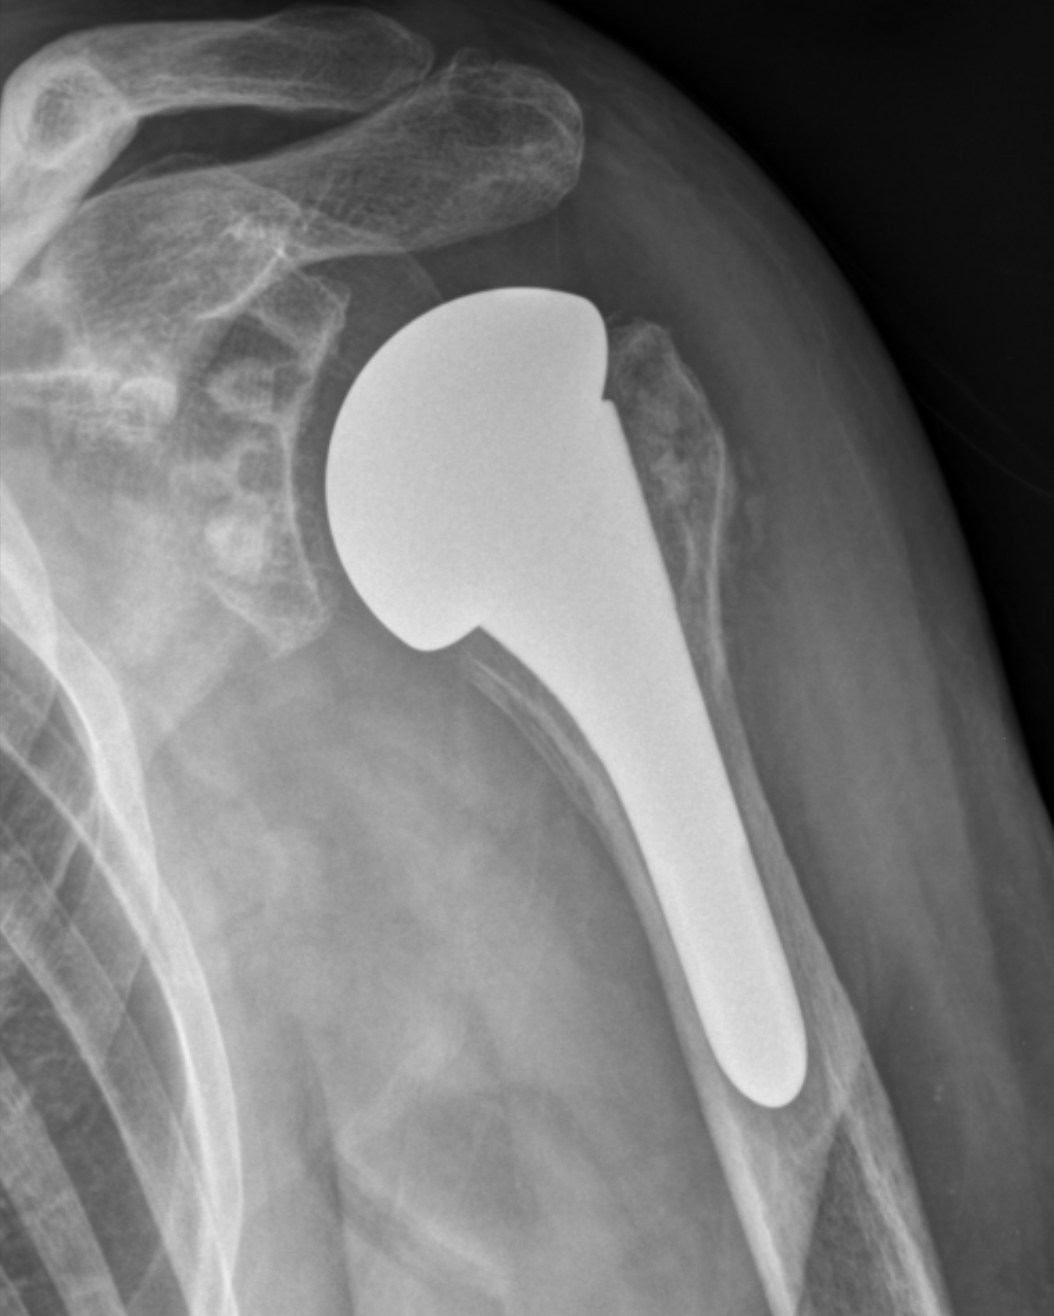

2. Anatomic Shoulder Replacement:

What to Expect with an Anatomic Shoulder Replacement? Click herePreserves the natural alignment of the shoulder and is typically used when the rotator cuff is intact.

In standard shoulder replacement, surgeons replace the ball at the top of the arm bone (humerus) with a metal ball, and the socket of the shoulder blade (scapula) with a plastic socket. However, this technique doesn’t work well when the rotator cuff is damaged, as it may lead to loosening of the implants.